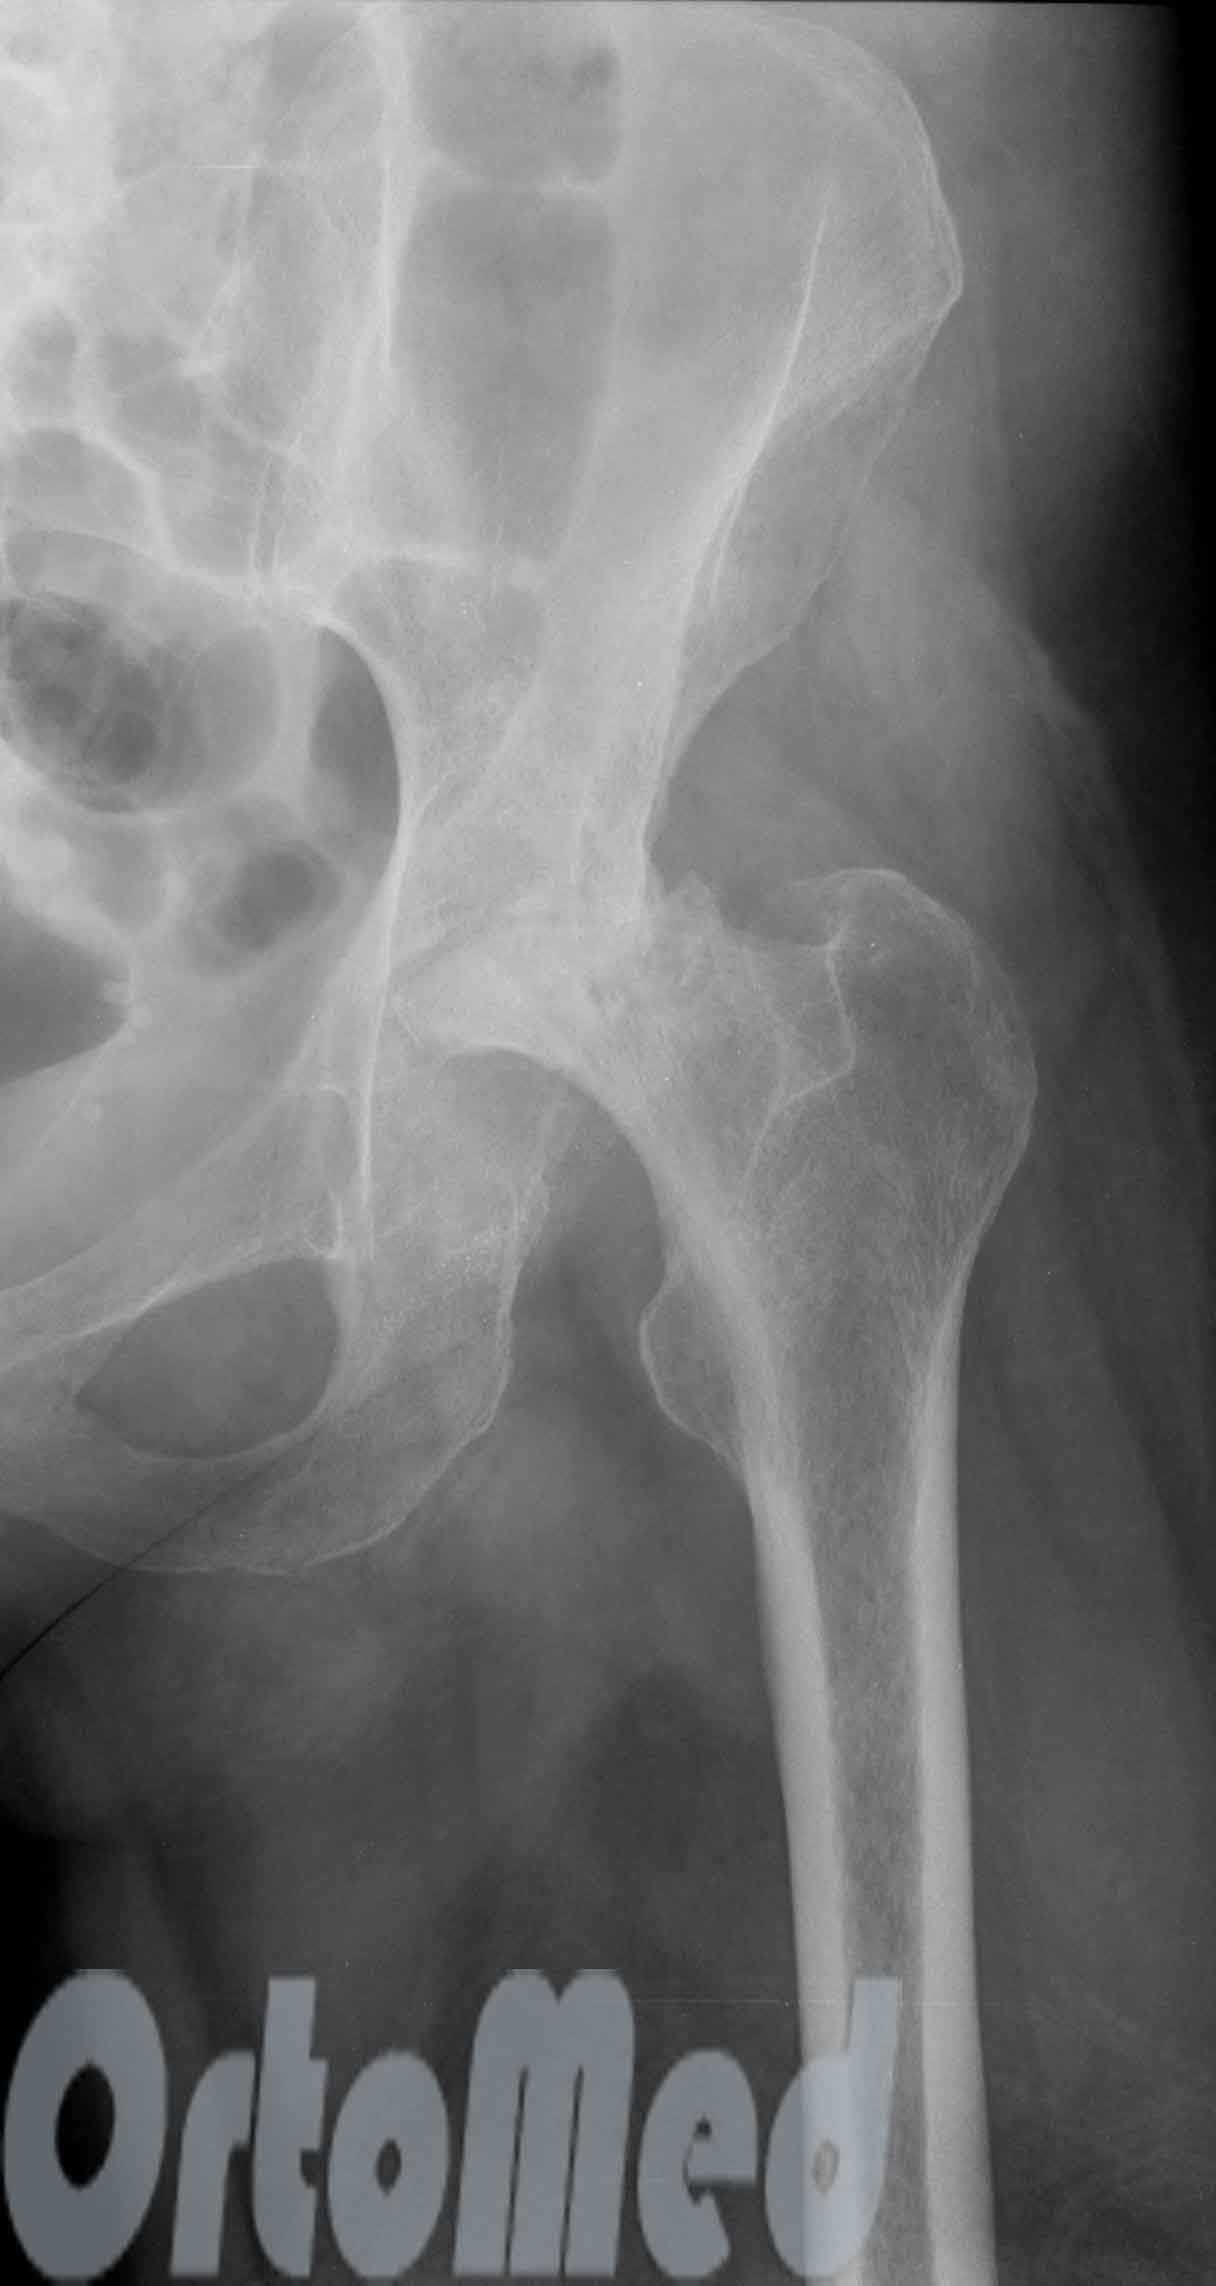

На данной рентгенограмме представлен двусторонний диспластический коксартроз (недоразвитие крыши вертлужной впадины с 2-х сторон)

Абдукционный перелом шейки бедренной кости слева

Асептический некроз головки левой бедренной кости